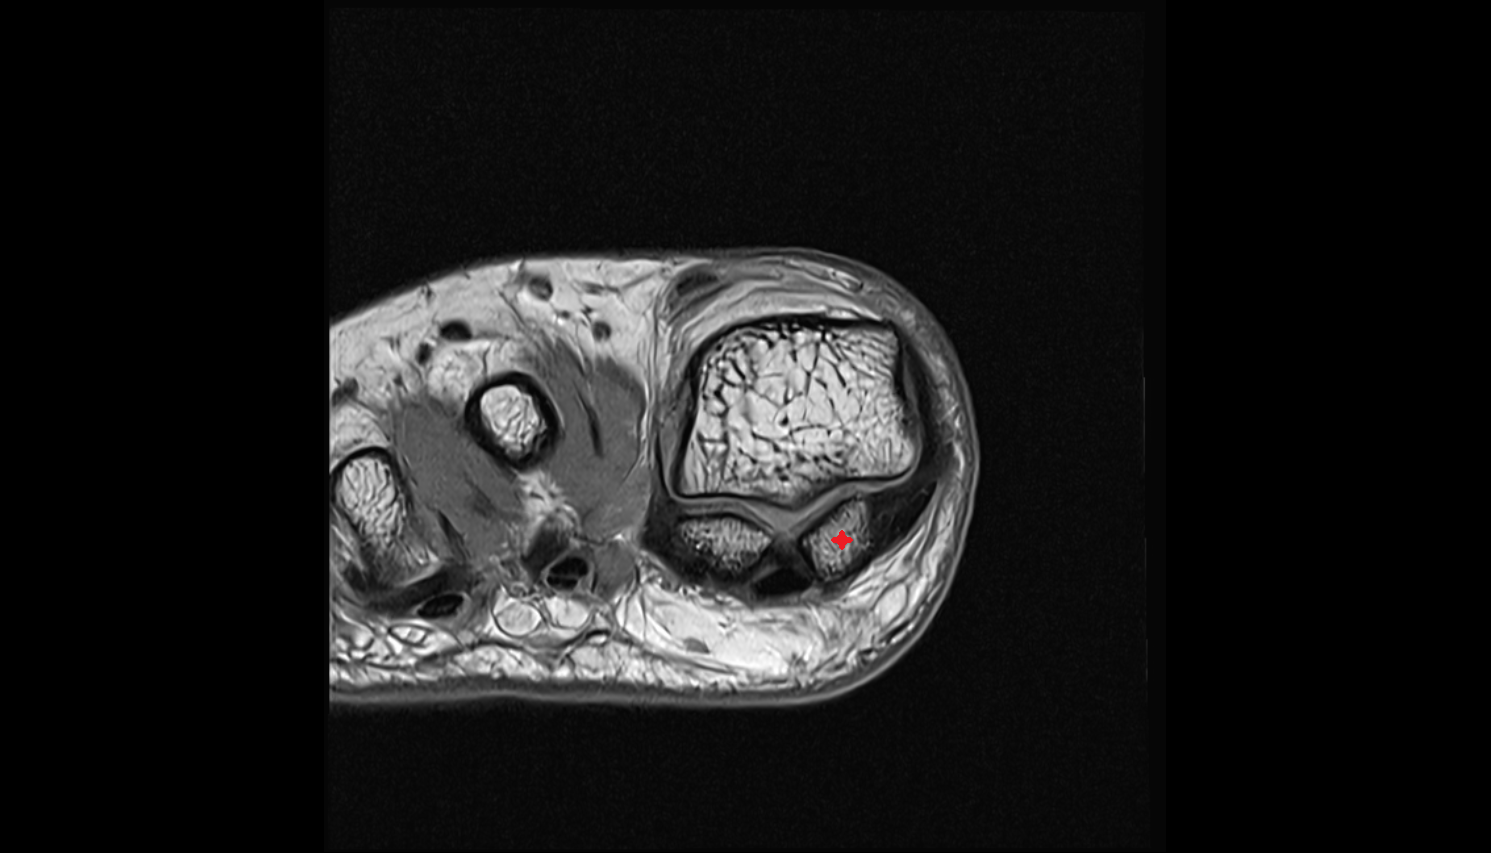

- Sesamoid bone of great toe

- Lateral sesamoid bone

- Medial sesamoid bone

- Metatarsophalangeal joints

- Flexor hallucis brevis muscle

- Lateral head of flexor hallucis brevis muscle

- Medial head of flexor hallucis brevis muscle